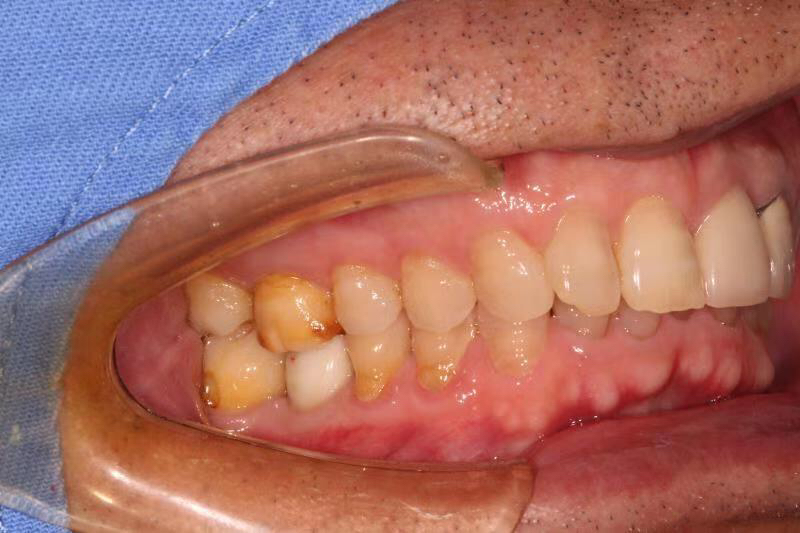

患者中年男性,左上中切牙外院烤瓷冠修复多年,因牙冠脱落前来就诊,由于牙冠制作不够密合,牙齿已经腐烂成残根,无法修复,只能进行种植修复,由于是门牙,我们在做完种植术后为患者制作了临时冠,最大程度保证了美观性。